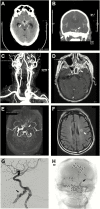

Background: Rhinosinusitis, malignant otitis externa, and skull base osteomyelitis represent a spectrum of cranial invasive fungal disease (IFD). These syndromes have distinct characteristics, yet they may progress to involve similar structures, resulting in inflammation and invasion of the adjacent internal carotid artery (ICA). Invasive fungal carotiditis can have devastating consequences, including cerebral infarction, subarachnoid hemorrhage, and death.

Results: We identified 78 cases of invasive fungal carotiditis between 1958 and 2018, including 4 cases at our own institution. Forty-one were caused by Aspergillus and 37 by Mucorales species. Presenting symptoms included vision changes (73%), cranial nerve palsy (69%), and headache (42%). Carotid events included occlusion, aneurysm formation, and vessel rupture. Cerebral infarcts occurred in 50% of cases. Mortality at 6 weeks, 12 weeks, and 2 years was 27%, 41%, and 71% respectively. The median time from symptom onset to death was 150 days for cases due to Aspergillus and 51 days for cases due to Mucorales species.

Conclusions: Invasive fungal carotiditis is a rare but morbid manifestation of cranial IFD. Early suspicion of IFD and administration of antifungal treatment, vascular imaging, and endovascular interventions should be considered to reduce the high mortality of this disease.